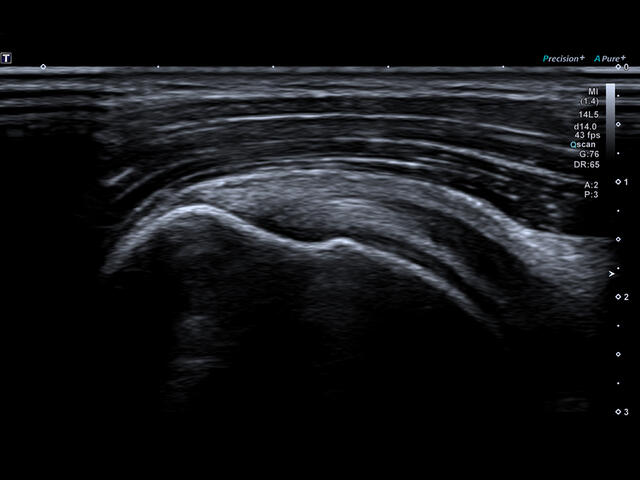

Aplio a550 – это многофункциональная УЗИ система экспертного класса. Высокое качество изображения и интуитивно понятный интерфейс поможет вам обеспечить высокую производительность и скорость проведения исследования.

Отличная цветопередача с высокой детализацией и четкостью изображения. Устройство подходит для профессионального использования в частных кабинетах и крупных медицинских центрах. Комплектация сканера применима для самых разных исследований. Широкий диапазон прикладного клинического программного обеспечения высокоэффективен для общих исследований, сердечно-сосудистых, гинекологических, ортопедических, урологических.

Aplio a550 может работать с линейным матричным датчиком и поддерживает новейшие монокристаллические датчики. Также Aplio a550 поддерживает большое количество дополнительных опций, таких как - SMI, Компрессионная эластография, Эластография сдвижной волны, Smart Fusion, исследования с использованием контраста (CEUS), 3D реконструкции в реальном времени (4D), функции автоматической оценки подвижности миокарда и фракции выброса.